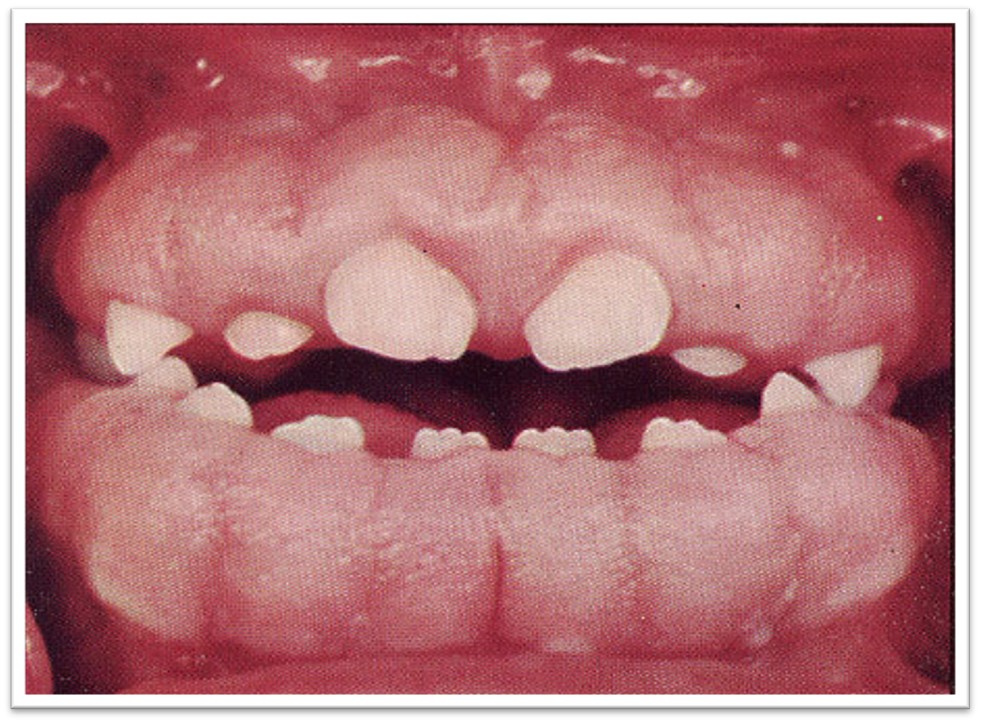

2)遗传性牙龈纤维瘤病( hereditarygingival fibromatosis)

②临床表现

牙龈呈弥漫性增生(图10.1-7)。

图10.1-7 遗传性牙龈纤维瘤病